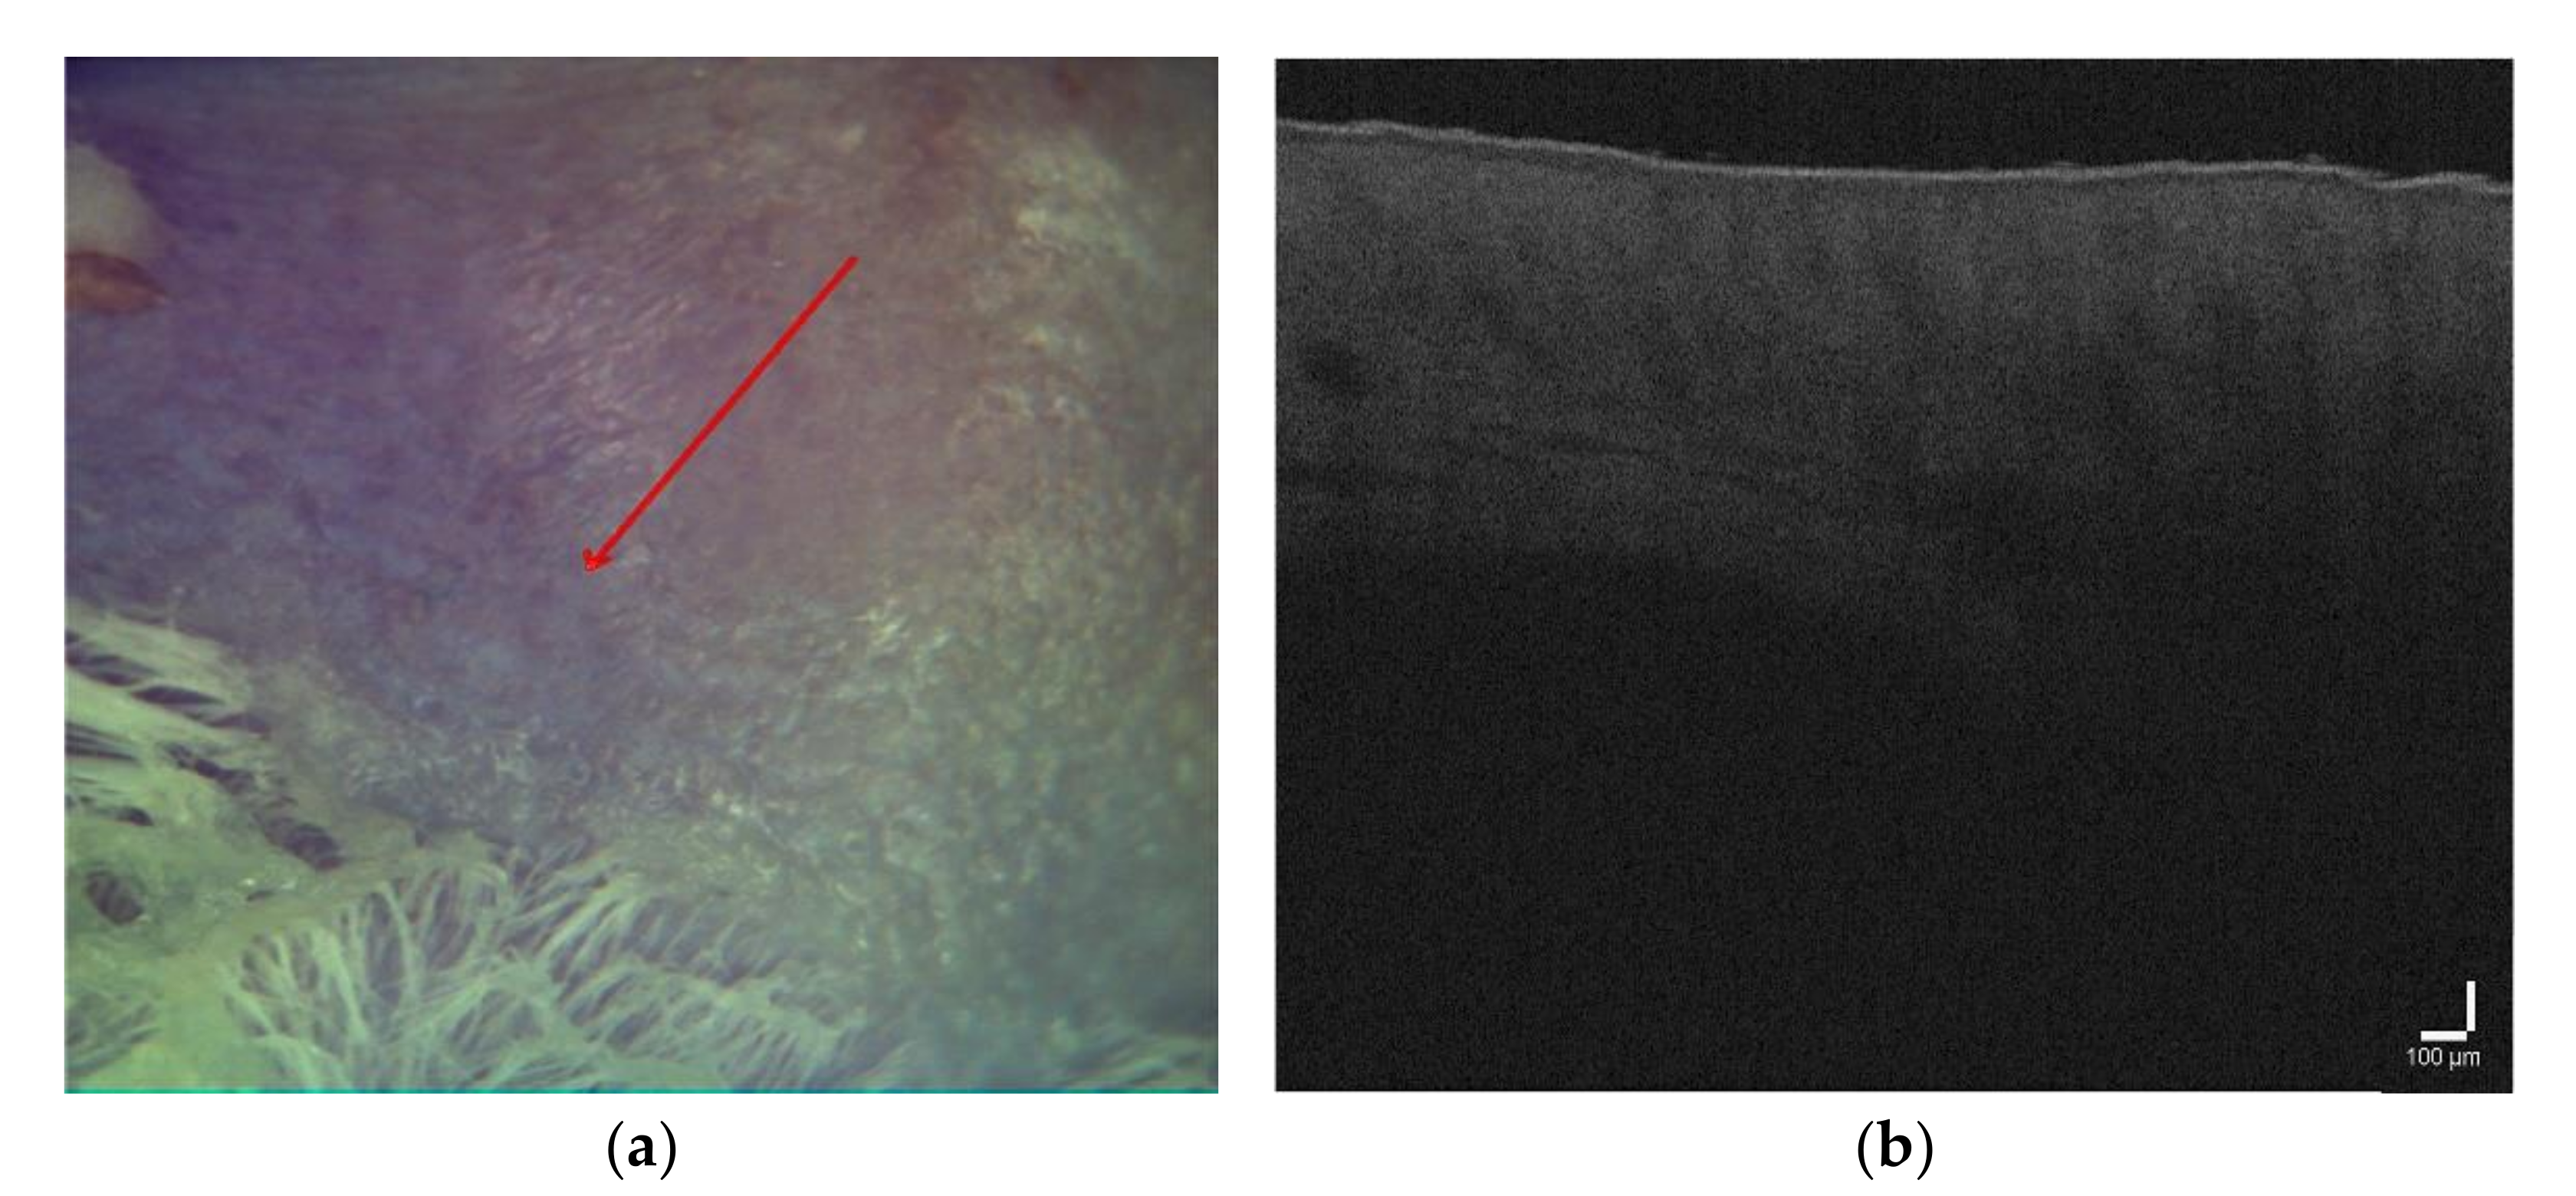

3.1. OCT Imaging